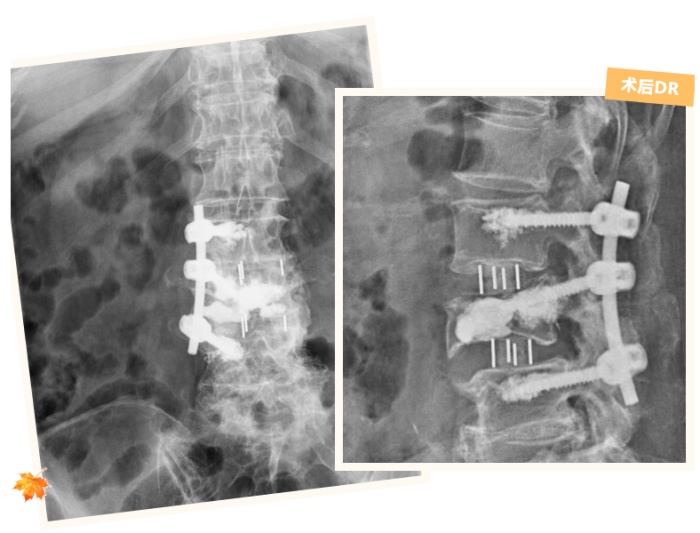

面對這樣的難題,脊柱外科團(tuán)隊沒有急于手術(shù),而是先反復(fù)研究張奶奶的影像檢查結(jié)果,結(jié)合她的癥狀、身體狀況和既往手術(shù)情況,經(jīng)過多次討論,最終制定了一套“精準(zhǔn)拆障、分步修復(fù)”的手術(shù)方案:第一步,通過腰椎間盤摘除術(shù),清除壓迫神經(jīng)的病變椎間盤組織,解決“神經(jīng)受壓”這個核心問題;第二步,采用椎管減壓術(shù)和神經(jīng)根擴(kuò)大減壓術(shù),進(jìn)一步拓寬神經(jīng)通道,徹底解除神經(jīng)受到的擠壓,讓麻木的右腿逐漸恢復(fù)知覺;第三步,實施后外側(cè)入路腰椎椎間植骨融合內(nèi)固定術(shù),在避開骨水泥的“安全區(qū)域”精準(zhǔn)打釘,既能固定彎曲的腰椎,又能重建腰椎的穩(wěn)定性,恢復(fù)腰椎的正常支撐功能。

術(shù)后經(jīng)過一段時間的康復(fù),復(fù)查時張奶奶已經(jīng)能夠獨立行走上百米。她開心地說:“現(xiàn)在腰不酸了,腿也不麻了,終于能像以前一樣正常出門散步了!”